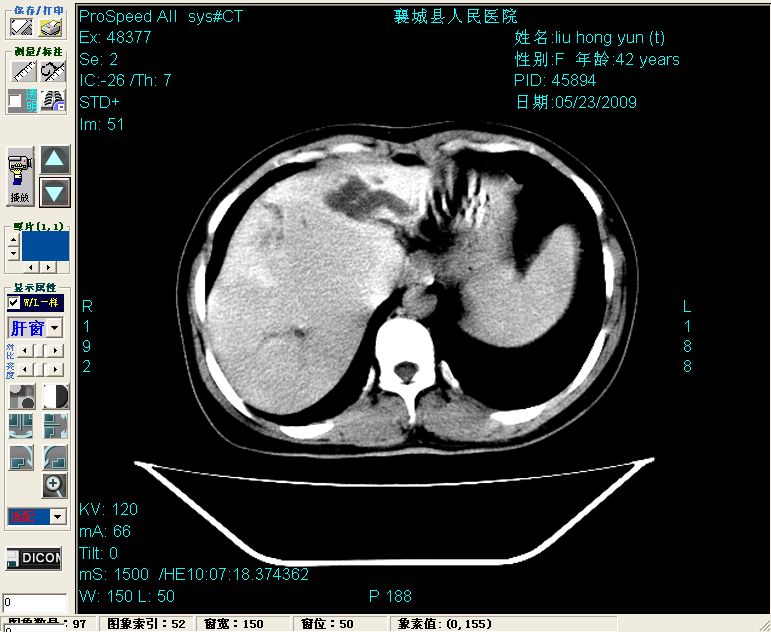

增强:

增强动脉期前述低密度区轻度早其强化,门脉期强化程度显著增高,延期扫描强化程度下降,但仍为相对高密度影

2左肝及右肝前叶表现考虑胆囊摘除术后所致的肝动门脉瘘形成,慢性纤维组织炎性增生.不完全除外左肝胆管细胞癌

1)肝内胆管结石,胆总管末端结石伴肝内胆管扩张。2)肝左叶及肝右叶前段增强前后之异常表现,考虑炎性改变,不排除胆管细胞癌。